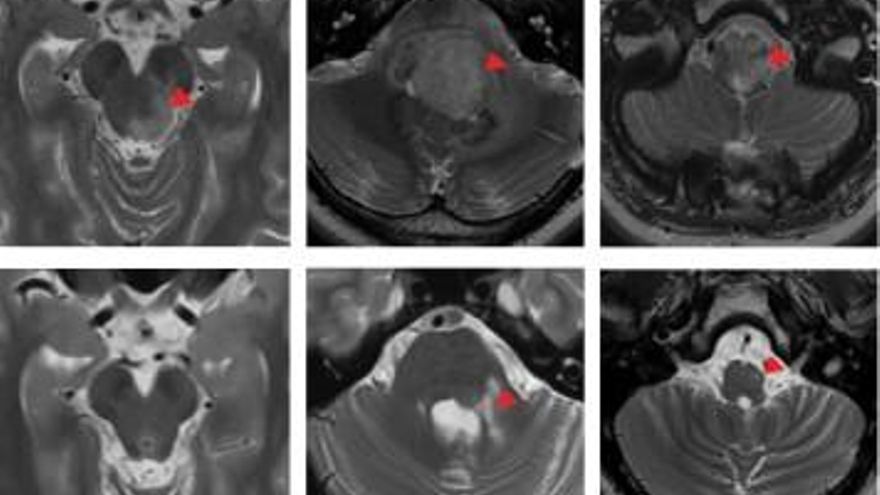

Detalle de un ensayo clínico.

2

En la revista Nature aparece como paciente 1.144 y, aunque no sabemos cómo se llama, es la persona con un cáncer avanzado tratada con terapias CAR-T que ha registrado la remisión más prolongada hasta la fecha. Han pasado 18 años desde que esa niña diagnosticada con un neublastoma, un tumor infantil difícil de tratar que afecta a las células nerviosas y tiene altas tasas de recaída, recibió el tratamiento. Hasta hoy la enfermedad –entonces estaba extendida a los huesos– ha permanecido en remisión, según el artículo recogido este lunes en la publicación científica, que cuenta su caso y el de otros 18 niños y niñas que formaron parte de un ensayo pionero realizado entre 2004 y 2009 en el Baylor College Medicine de Texas (Estados Unidos).